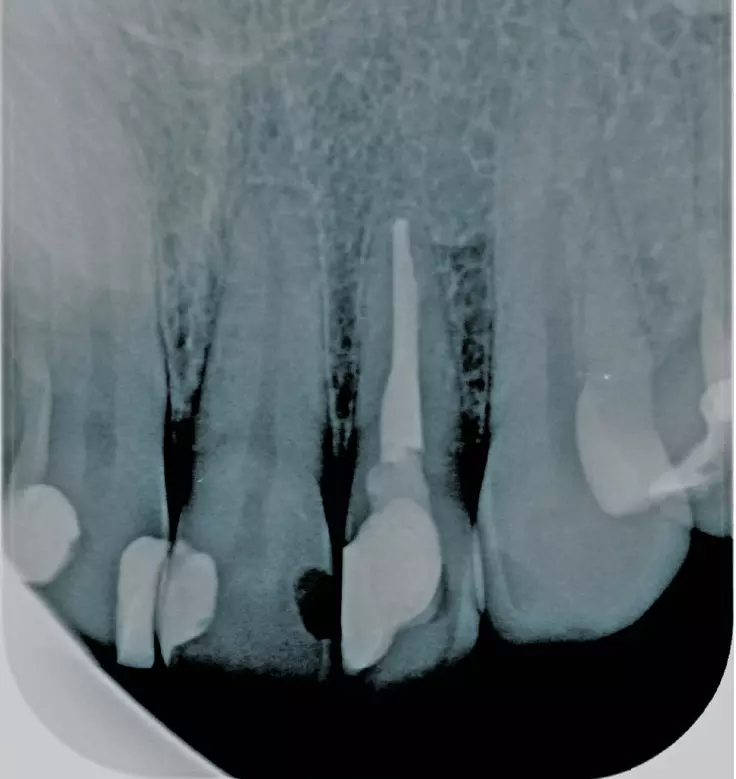

Lipopolysacharide (LPS) in Bakterienmembranen der Parodontopathogenen als auch Titanpartikel stimulieren Inflammasome in den Makrophagen (Abb. 4) und verursachen eine IL-1b-Ausschüttung. Der Effekt der Stimulation durch Titanpartikel war bei LPS-exponierten (Aa, Pg, e.coli) Makrophagen verstärkt. Titan- Ionen allein führen nicht zur Transkription der Inflammasome. Die in periimplantären Geweben gefundenen Ti-Mengen waren ausreichend um die IL-1b-Ausschüttung in-vitro zu stimulieren [38,39].

Dr. Jacobi-Gresser